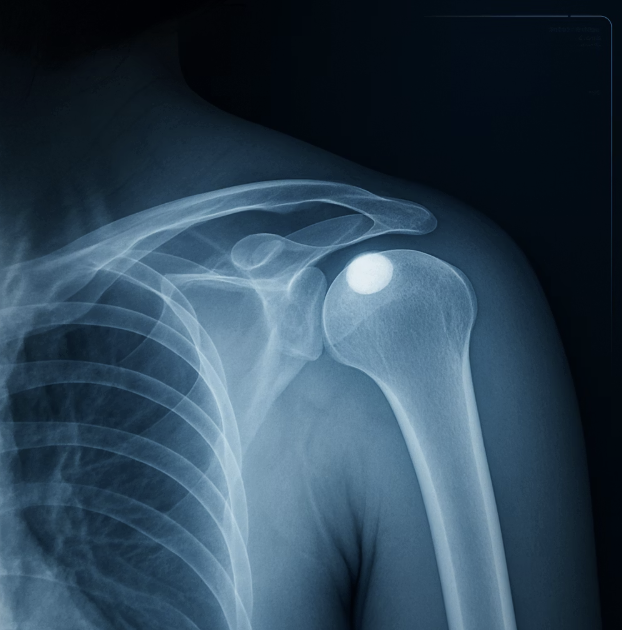

Q. 엑스레이(X-ray)만 찍어봐도 알 수 있나요?

A. 네, 그렇습니다. 석회성건염은 엑스레이 검사만으로도 비교적 쉽게 진단이 가능합니다. 석회는 뼈와 비슷한 성분이라, 엑스레이 사진에서 어깨 힘줄 부위에 하얀 돌멩이처럼 뚜렷하게 보이기 때문입니다.